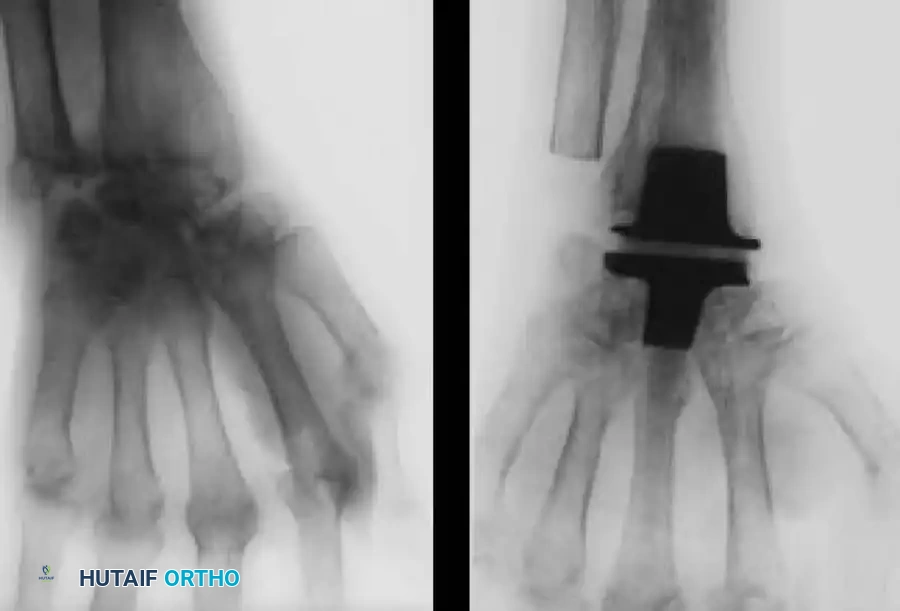

Silicone Implant Arthroplasty (Swanson)

Silicone spacer arthroplasty remains a viable option for low-demand rheumatoid patients with advanced disease (Stage III or IV) and poor bone stock that precludes the use of metal-on-plastic total wrist systems. The procedure requires minimal bone resection and acts as a dynamic spacer to maintain alignment while a fibrous capsule forms.

Image

While pain relief is initially excellent, surgeons must counsel patients on the high complication rates associated with silicone implants over time. Long-term studies indicate a prosthetic fracture rate ranging from 10% to 52%, and progressive radiographic settling with bone resorption in up to 75% of cases. Despite these radiographic failures, clinical satisfaction often remains acceptable in low-demand individuals.